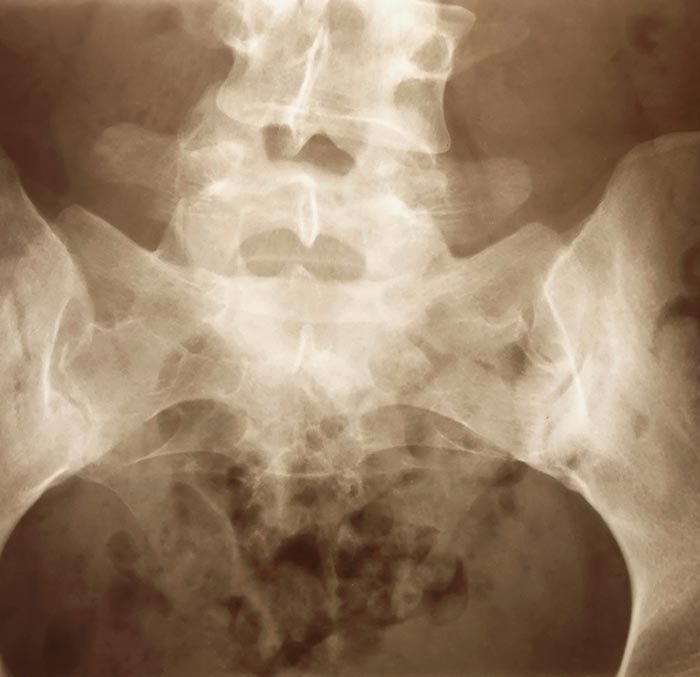

Si presentas síntomas de rigidez matutina, limitación o disminución de la movilidad, dolor crónico, enrojecimiento, hinchazón y calor en las articulaciones, es posible que sufras alguna enfermedad reumática.

Es experto en la atención de enfermedades como artritis, osteoporosis, artrosis, ciática y lumbago, las cuales son de las enfermedades reumatoides más comunes.

medicina interna y en el diagnóstico y tratamiento de otras enfermedades complejas de reumatología como el

lupus y la

fibromialgia para poder realizar un manejo eficaz que evite daños articulares permanentes o discapacidad.